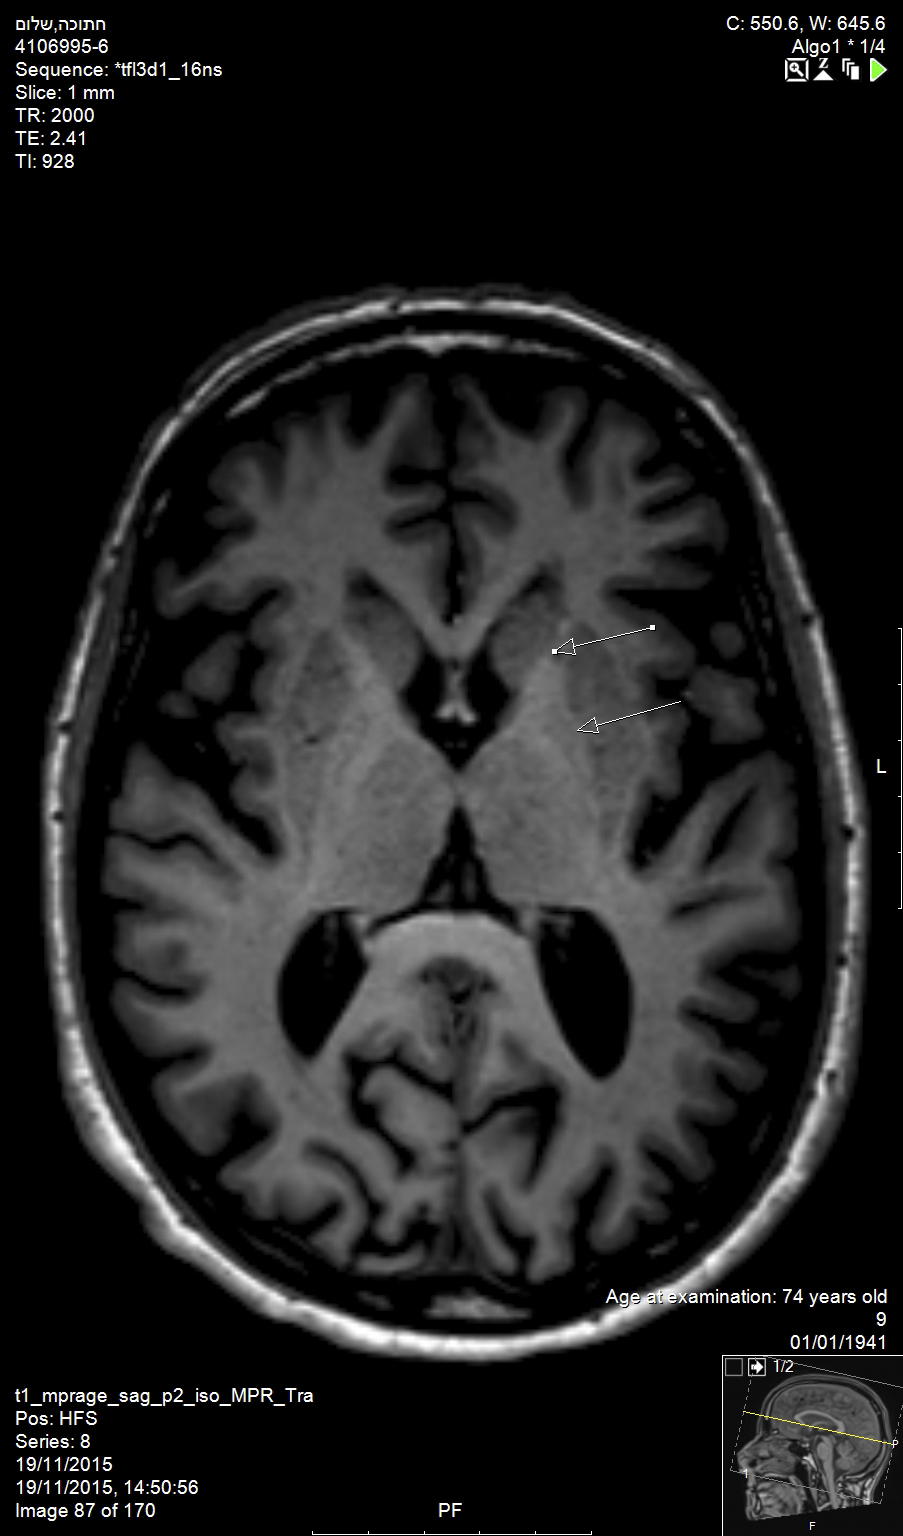

In the brain, Alzheimer’s disease and Huntington’s disease result in widespread loss of neurons (Figure 1), while Parkinson’s disease involves the specific and localized loss of dopaminergic neurons in the substantia nigra. In the brainstem and spinal cord, amyotropic lateral sclerosis and spinal muscular atrophy involve the degeneration and loss of motor neurons. While all of these conditions exhibit unique neuronal pathologies, the exact mechanisms for neuronal loss are complex, making the identification of efficacious treatments elusive.1

Huntington’s disease is named after George Huntington, the physician who described it as hereditary chorea in 1872. It is an incurable, adult-onset, autosomal dominant inherited disorder associated with cell loss within a specific subset of neurons in the basal ganglia and cortex.3 The most striking neuropathology in Huntington’s disease occurs within the neostriatum (Figure 2), in which gross atrophy of the caudate nucleus and putamen (Figure 3) is accompanied by selective neuronal loss and astrogliosis. Marked neuronal loss is also seen in deep layers of the cerebral cortex.4 The clinical features include a movement disorder, cognitive disorder, dementia, and behavior disorder. Patients may present with one or all disorders in varying degrees.5

Fig 1. Alzheimer’s disease and Huntington’s disease result in widespread loss of neurons, as shown in this magnetic resonance image (MRI) of the brain of an elderly patient (top arrow: head of caudate nucleus; bottom arrow: putamen).